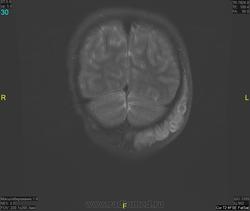

Уважаемые коллеги! Прошу консультативной помощи. Про пациента известно: девочка (7 лет), в анамнезе 2,5 года назад травма головы. Не диагностировалась. Периодически жалобы на болезненность при пальпации затылочной области(((((

Напоминает сосудистую структуру.Может, какая-нибудь лимфангиома?Видела на передней поверхности шеи, на задней - нет.

как будто связь с ликвором имеется.  Дополнил бы венографией, и FatSat"ом ну и контрастом, конечно.

Сегодня в ходе разговора с мамой девочки, выяснилось, что и у мамы есть подобное "образование". С ее слов, несколько лет назад ей делали пункцию для исключения онкологии. Результат пункции: содержится нервная ткань и лимфоциты ( опять же никаких документов я не видела). То есть можно говорить о наследственном характере.

Нейрофиброма вполне может быть. Плексиформная. Проверить на нейрофиброматоз. Я видел такой же структуры и локализации. Пятен на коже нет? Вообще на теле? И нет ли чего похожего в позадиглоточном пространстве?

есть похожее образование в позадиглоточном пространстве)

многоузловое образование  исходящее из задней части предпозвоночного пространства с переходом на подкожную жировую клетчатку головы!шваннома ,нейрофиброма и их злокачественные аналоги